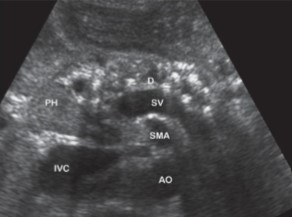

This image was taken in what plane?

Explain your answer.

Sagittal

The pancreas head is the only part visualized